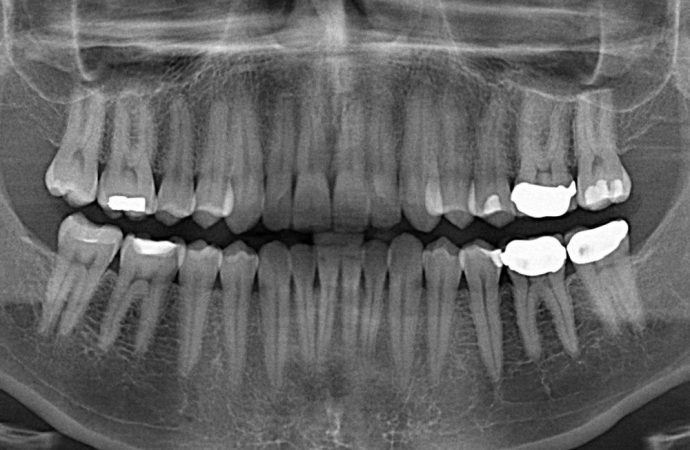

Dentists treat hundreds of millions of cavities each year by drilling out the decay and putting in a filling.

But 10 to 15 percent of those fillings fail, says Adam Celiz, a therapeutic biomaterials researcher from University of Nottingham. And that leads to millions of root canals to remove the tooth’s pulp, the soft tissue in the center of the tooth that contains the blood vessels, nerves, and connective tissue. A root canal can weaken the tooth, which may eventually need to be pulled.

In in vitro testing, the fillings stimulated the proliferation and differentiation of stem cells into dentin, the bony tissue that forms the bulk of the tooth under the white enamel. The researchers believes that if used in a damaged tooth, those stem cells can repair the kind of damage that often comes from the installation of a filling. In essence, the biomaterial filling would allow the tooth to heal itself.